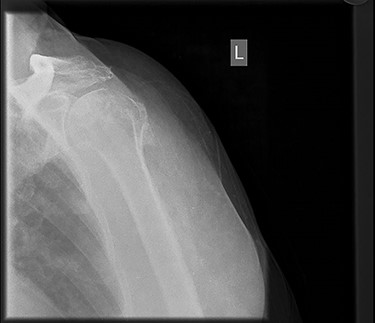

X-ray imaging showed degenerative changes in the glenohumeral and acromioclavicular articulations.

X-ray imaging showed degenerative changes in the glenohumeral and acromioclavicular articulations with inferior displacement of the humeral head.